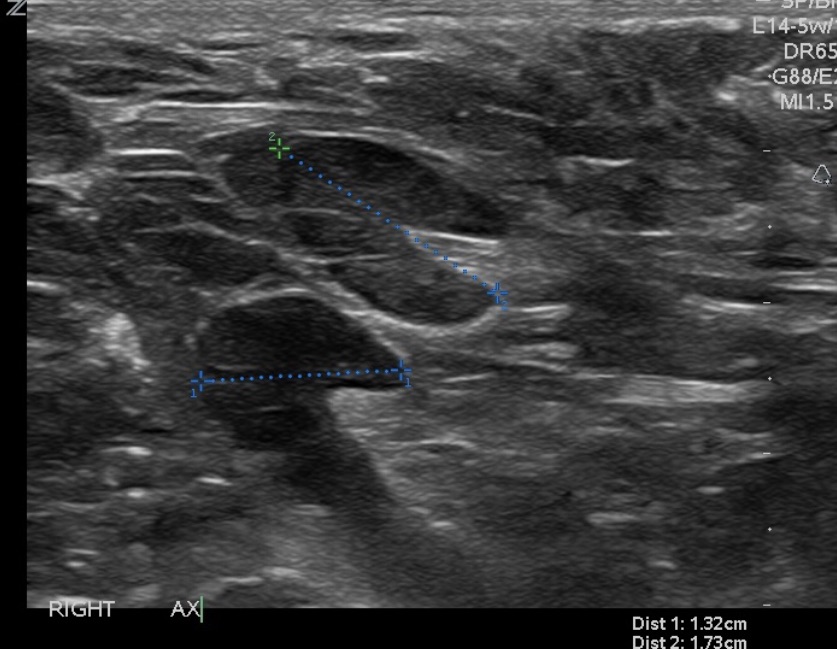

• Before the node reaches the stage of complete replacement:

• It can have an asymmetric, thickened cortex, with an eccentric hilum (Image)

Lymph nodes with eccentric hila and asymmetric, thickened cortices.